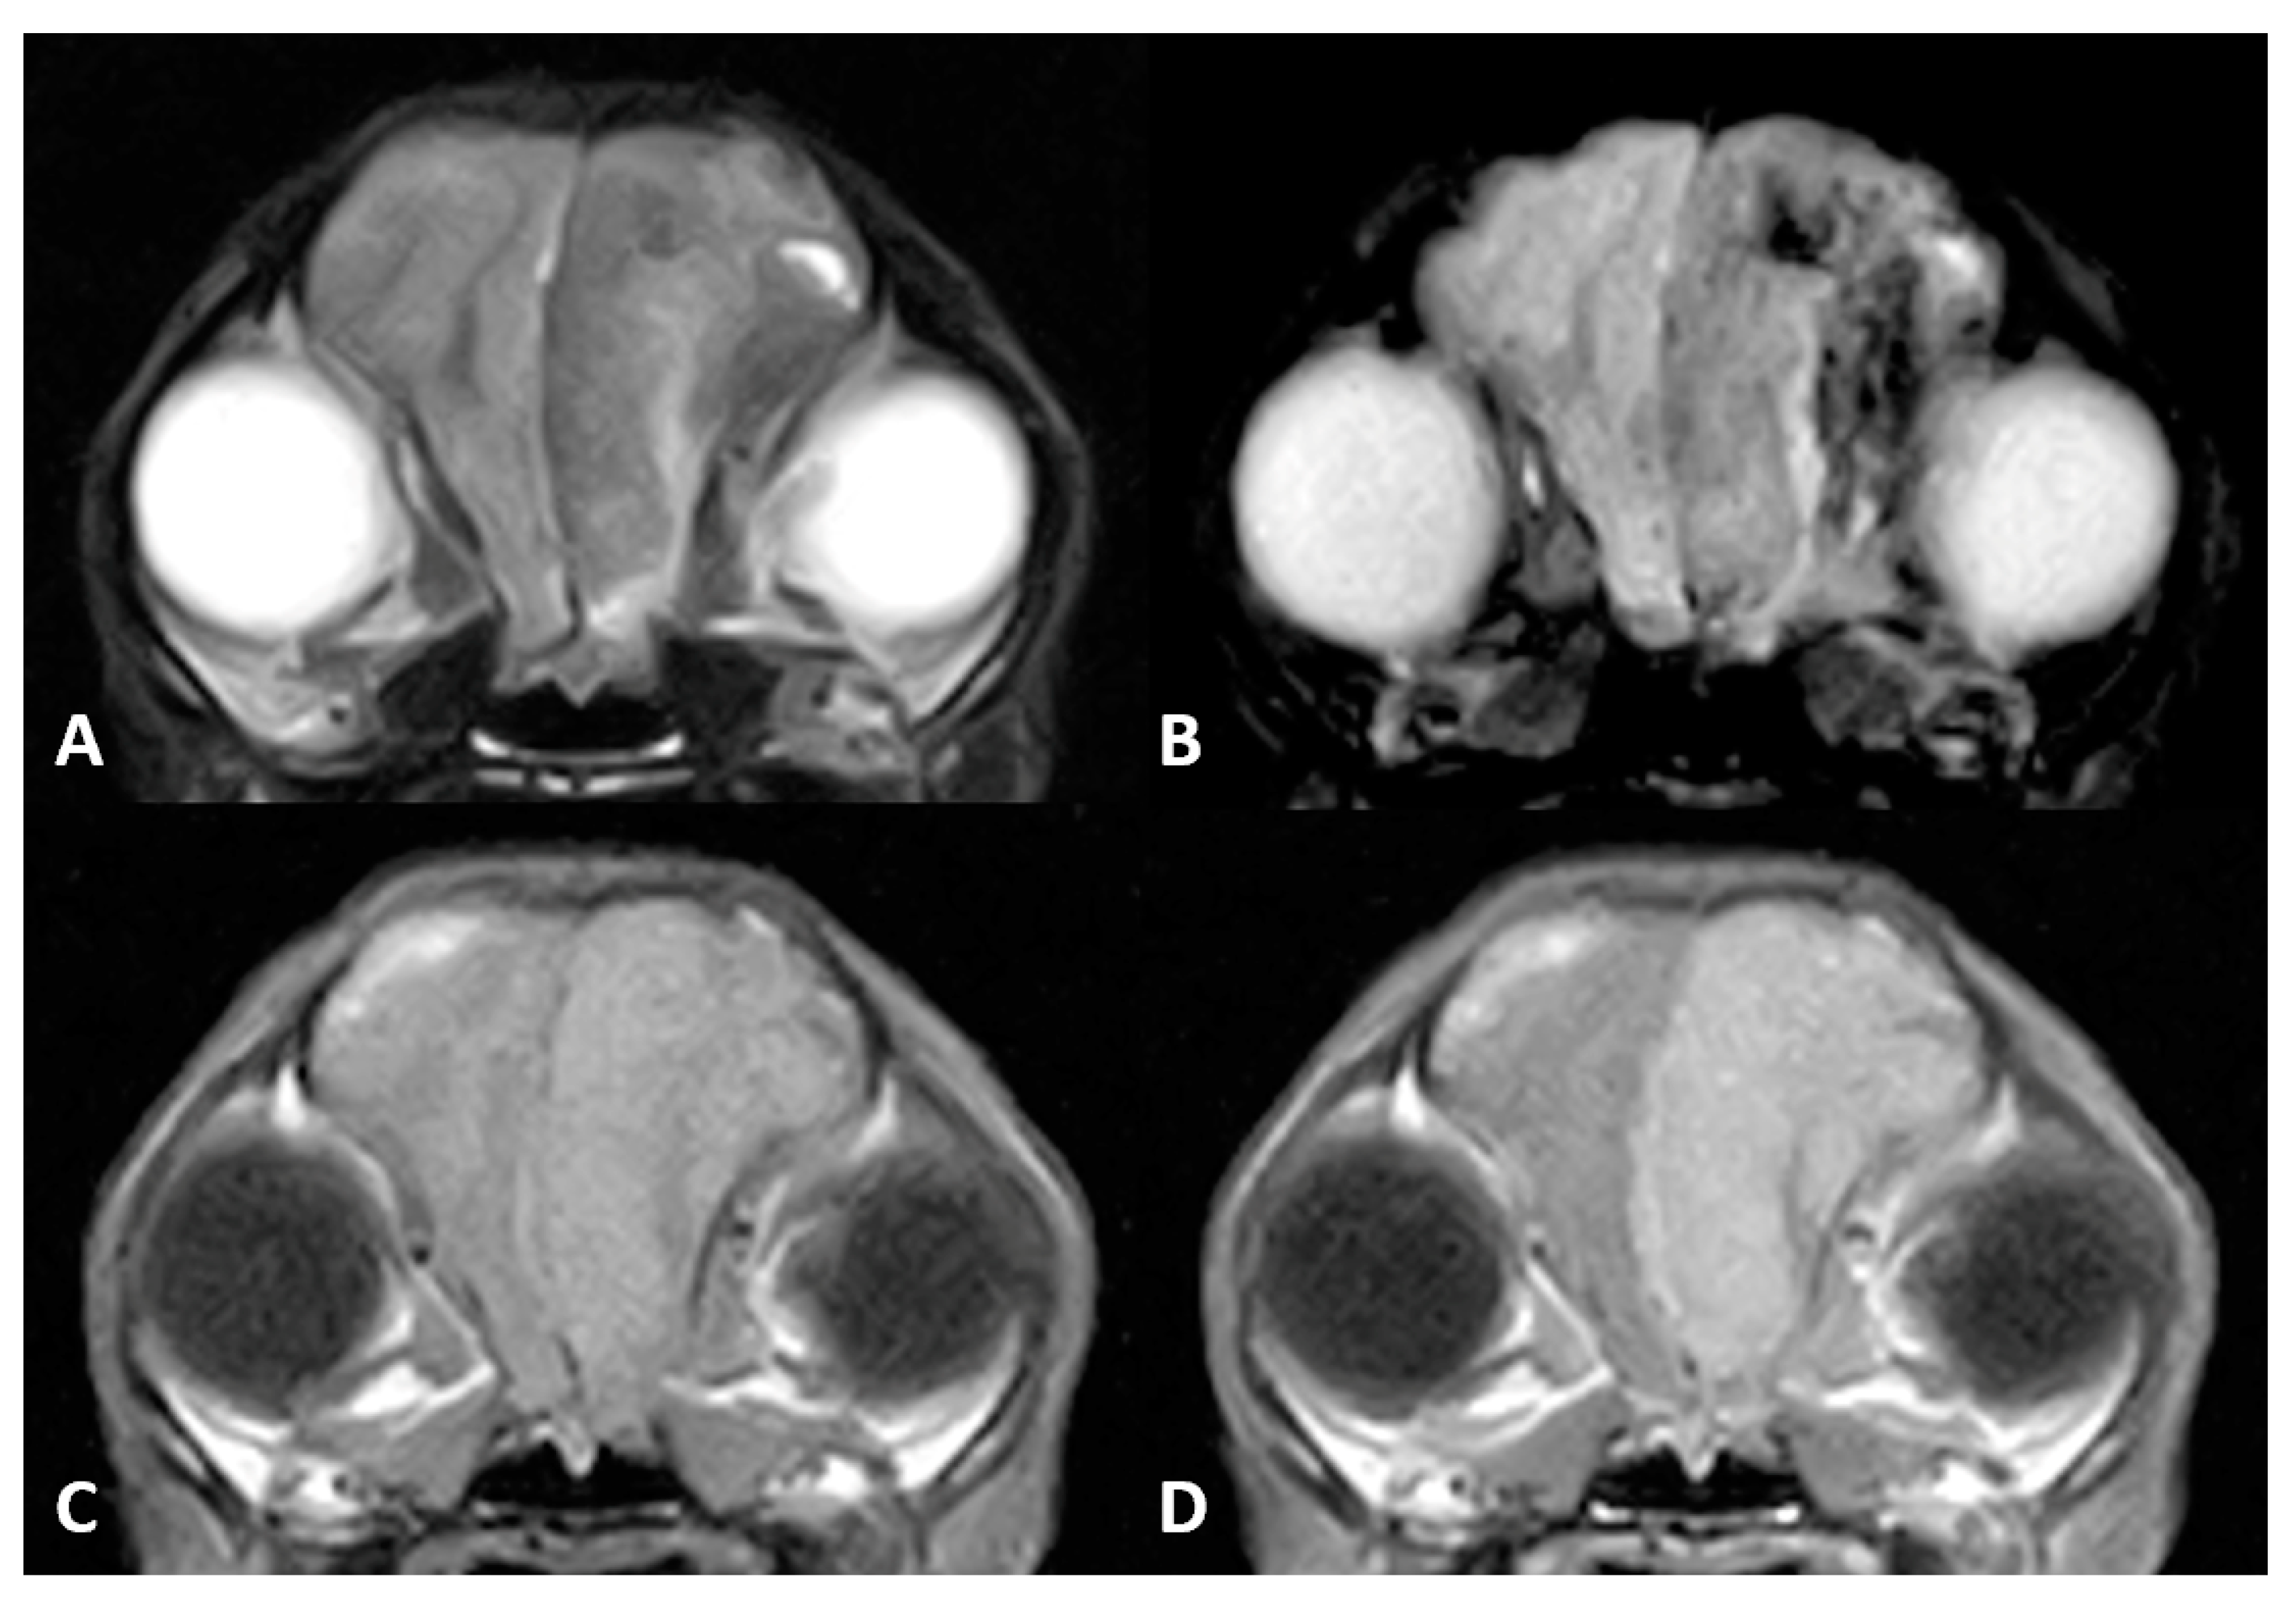

A routine MR imaging study was performed with T1w, T2w, fluid attenuation inversion recovery (FLAIR), postcontrast T1 (T1w+c), gradient echo (T2*) transverse sequences (see Figure 1), and T2w, T1w and T1w+c sagittal sequences.

Diffuse thickening of the meninges covering the left hemisphere was seen. A plaquelike lesion extending from the left olfactory bulb involving the meninges along the convexity of the whole hemisphere, extending to the falx cerebri and affecting partially the adjacent right cerebral hemisphere, was observed. The mass was markedly hypointense with respect to grey matter on T2w, FLAIR and T2* sequences, isointense on T1w with focal areas of hyperintensity, and showed marked and uniform enhancement after contrast administration. Adjacent to this lesion, mild diffuse T2w and FLAIR hyperintensity was present affecting the brain parenchyma. The lesion was causing a severe mass effect over the left lateral ventricle and subfalcine brain herniation of the left cerebral hemisphere. The cerebral sulci of the affected side were moderately attenuated, suggesting increased intracranial pressure.

Figure 1. Magnetic resonance (MR) imaging of the brain of Case 1, transverse images at the level of the thalamus. A plaquelike extra-axial mass is visible covering the left hemisphere with (A) a marked hypointense signal on T2-weighted (T2w) sequences and (B) fluid attenuation inversion recovery (FLAIR). (C) T1-weighted (T1w) hyperintensity was not visible, but (D) marked enhancement after contrast administration could be detected. Note the severe mass effect and peritumoral oedema causing occlusion of the left lateral ventricle.